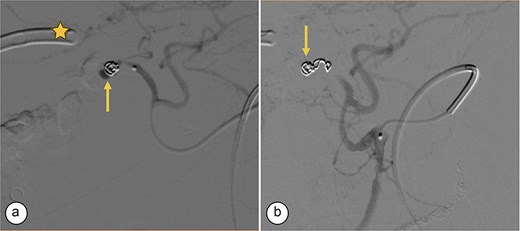

Surgical reconstruction revealed an excluded PRHD and ARHD–LHD continuity with obstruction 10 mm from the confluence. The PRHD catheter was found outside the biliary tract, so a transhepatic Nelaton catheter was placed from inside to out. A neoconfluence of PRHD with ARHD and LHD was created with a 30 mm hepaticojejunostomy. A transanastomotic Nelaton catheter and a supranastomotic ARHD catheter were left in place. Estimated blood loss: 300 cc. In the immediate postoperative period, the patient developed melena and bleeding from the Penrose drain. Cholangiography via the right percutaneous catheter showed no contrast leakage. Angio-CT revealed an 8 × 5 mm saccular lesion in the anterior right hepatic artery (Segment V), consistent with a pseudoaneurysm (Figs 1 and 2). Selective embolization with three microcoils (2 × 3 × 2.3 mm) was successfully performed (Fig. 3). The patient had a favorable recovery, with no further bleeding, and was discharged in stable condition for outpatient follow-up. Control imaging of the ARHD catheter confirmed adequate visualization of all hepatic ducts, allowing catheter removal (Fig. 4).

Transcatheter arterial embolization of the right hepatic artery. (a) Selective transcatheter arterial embolization (TAE) of the branch of the right hepatic artery (Segment V) (arrow). (b) Post-embolization image of the pseudoaneurysm in the branch (Segment V) of the right hepatic artery with microcoils (arrow), showing no contrast medium leakage. Right percutaneous catheter (star).